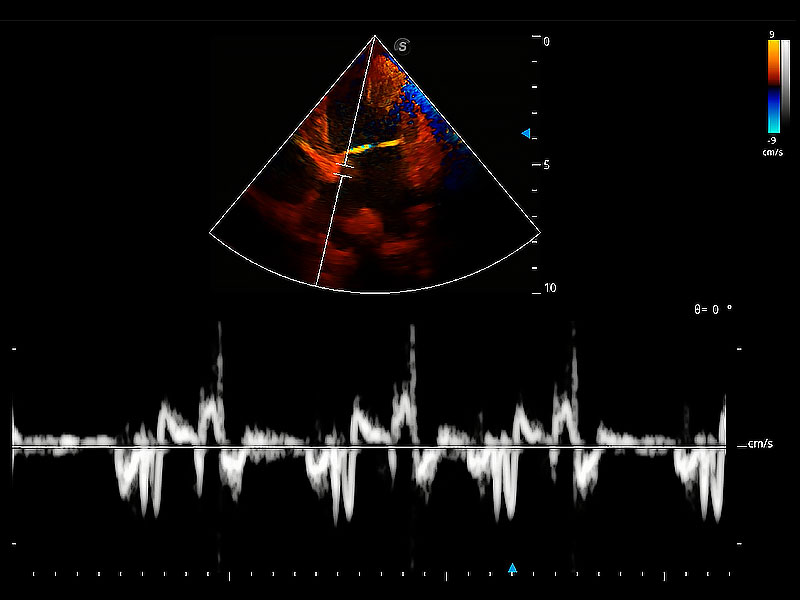

• TDI 組織多普勒成像

實時用顏色表示心肌組織運(yùn)動,觀察和定量組織的運(yùn)動情況,對快速檢測與評估心肌的灌注和活性、電傳導(dǎo)及心肌收縮和舒張功能等均能提供重要的診斷信息。

(犬)二腔心血流